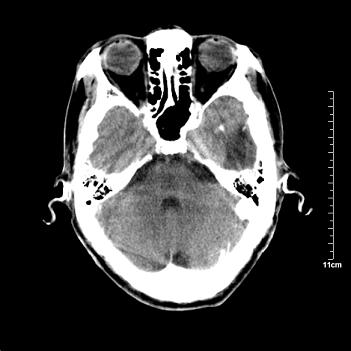

男性患者,72岁,近两天头晕来我院就诊。 因患者血压太高而未做增强,建议病人去市医院做mri检查。等得到mri随访结果再公布给大家。 测及左颞顶枕叶病灶ct值分别为5hu 30hu 729hu。

考虑左侧颞顶枕叶少突胶质细胞瘤。 今天随访患者手术病理结果 病理回报为胶质瘤2级 钙化

左侧颞顶枕叶大片状低密度影,呈均一水样密度,边界清楚,病灶边缘不规则片状钙化,左侧脑室后角扩大,中线结构未见移位,综合来看不像肿瘤,软化灶,钙化不好解释

左侧颞顶枕叶巨大囊性病灶,灶内见小片实性区且灶内及灶周围大量团块状钙化影,灶周水肿少.左侧室枕角内见环形钙化,可见较清晰前壁,钙化与室壁似有间隙.

考虑1寄生虫病2表皮样囊肿钙化3血管畸形,其他不排